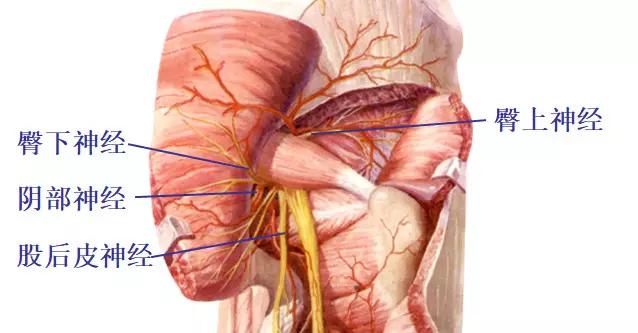

骶 丛

1.骶丛的组成和位置:L4.5 S1-5 Co1

2.骶丛的分支

臀上神经(L4,L5,S1)

臀下神经(L5,S1,S2)

股后皮神经(S1-S3)

阴部神经(S2-S4)